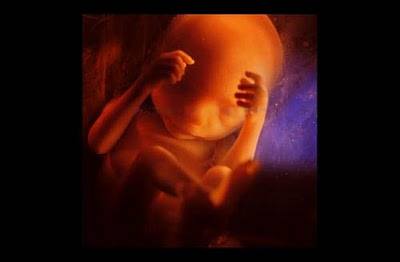

Պտուղն արդեն 16 շաբաթական է:

16 շաբաթական պտուղն սկսում է օգտագործել ձեռքերը, որպեսզի ուսումնասիրի սեփական մարմինը: